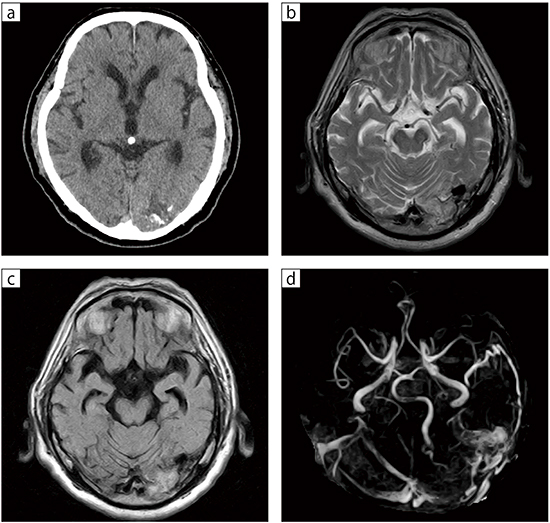

■症例1:硬膜動静脈瘻

75歳,男性。車の運転中に視野障害を認め受診。頭部CTで左後頭葉に多数の点状の石灰化と,その周辺に脳浮腫と思われる低吸収域を認めた(a)。MRIのT2WI,FLAIRでは浮腫と思われる高信号域を認め,多数の拡張した血管によるflow voidを認める(b,c)。MRAでは,拡張した硬膜枝と後頭動脈から静脈洞・脳表静脈への異常血流を認める(d)。

a:CT

b:T2WI,TR/TE=5000/100,スライス厚:6mm,FOV:220mm,FA:90°

c:FLAIR,TR/TE/TI=8000/90/1800,スライス厚:6mm,FOV:220mm,FA:90°

d:MRA MIP,TR/TE=33/6.5,スライス厚:1.3mm,FOV:180mm,FA:30°